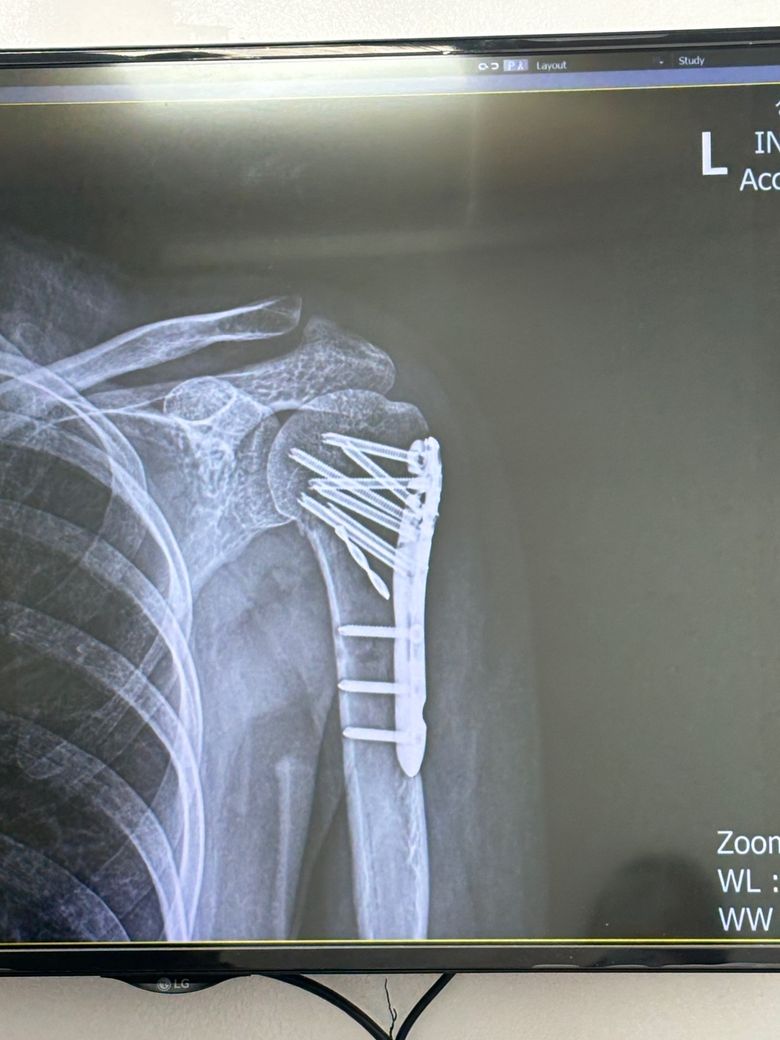

의료사고인지 사진좀 봐주세요…..

상완골 골절로 수술을 받았는데

엑스레이 사진에 드릴피스같은게 하나가 들어있는데 이거 뭔가요.. 1년뒤에 피스 제거수술할때 뺄수 있을까요?

뭔가 잘못된거 맞죠?

엑스레이에 보이는 드릴피스처럼 생긴 것은 수술 시 고정용으로 사용하는 나사나 일시적 가이드핀일 가능성이 큽니다.

이런 금속은 골절 부위 안정화를 위해 일부러 넣는 것으로 흔히 사용하는 방법이에요 제거 수술 시에는 보통 판과 나사 전체를 함께 빼게되므로 따로 남지 않습니다. 따라서 잘못된 게 아니라 정상적인 고정 방식일 가능성이 높습니다!

올려주신 사진에서 보이는 물체는 골절 수술 시 구조가 불안정 하거나 뼈조각이 많은 경우에 나사의 길이나 방향을 다양하게 배치하는 과정에서 사용되는 의료용 나사일 가능성도 배제할수는 없습니다.

현재 말씀하신 드릴피스처럼 보이는 것은 수술 중에 뼈 조각을 임시로 고정하기 위해 넣는 와이어나 보조용 고정 핀일 가능성도 있어서 수술한 병원에서 자세한 상황에 대해 확인해 보시는 것이 좋겠습니다.